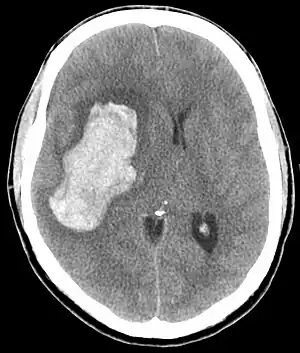

| CT scan of an intracranial hemorrhage, a possible complication of hypertensive emergency. | |

In the brain, hypertensive encephalopathy - characterized by hypertension, altered mental status, and swelling of the optic disc - is a manifestation of the dysfunction of cerebral autoregulation. Cerebral autoregulation is the ability of the blood vessels in the brain to maintain a constant blood flow. People with chronic hypertension can tolerate higher arterial pressure before their autoregulation system is disrupted. Hypertensives also have an increased cerebrovascular resistance which puts them at greater risk of developing cerebral ischemia if the blood flow decreases into a normotensive range. On the other hand, sudden or rapid rises in blood pressure may cause hyperperfusion and increased cerebral blood flow, causing increased intracranial pressure and cerebral edema, with increased risk of intracranial bleeding.[11]

Consequences of hypertensive emergency result after prolonged elevations in blood pressure and associated end-organ dysfunction. Acute end-organ damage may occur, affecting the neurological, cardiovascular, kidney, or other organ systems. Some examples of neurological damage include hypertensive encephalopathy, cerebral infarction, subarachnoid hemorrhage, and intracranial bleeding. Cardiovascular damage can include myocardial ischemia, acute left ventricular dysfunction, pulmonary edema, and aortic dissection. Other end-organ damage can include acute kidney failure, retinopathy, eclampsia, and microangiopathic hemolytic anemia.